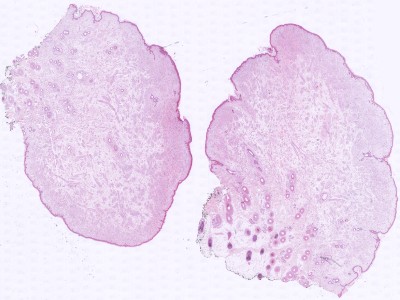

PA:

Golvend verlopend fibrillair weefsel met talrijke spoelvormige kernen, soms moeilijk te onderscheiden van fibromen. De afwezigheid van elastinevezels en de aanwezigheid van vele mestcellen is typisch voor neurofibromen. Een ander typisch kenmerk zijn veranderingen in het fibrillaire weefsel zoals vettige en myxoedemateuze degeneratie. Met kleuringen (o.a. S100) zijn merghoudende en mergloze zenuwvezels vaak aantoonbaar in neurofibromen. Vaak aanwezigheid van lymfocyten, plasmacellen, en melanofagen.

Histologie neurofibroom Histologie neurofibroom Histologie neurofibroom, S100 kleuring

ingescande coupe (zoom) ingescande coupe (zoom) ingescande coupe (zoom)

Bron hoge resolutie PA-foto's: Kevin Kwee en Afdeling Pathologie MUMC. Klik op de afbeelding om in te zoomen.